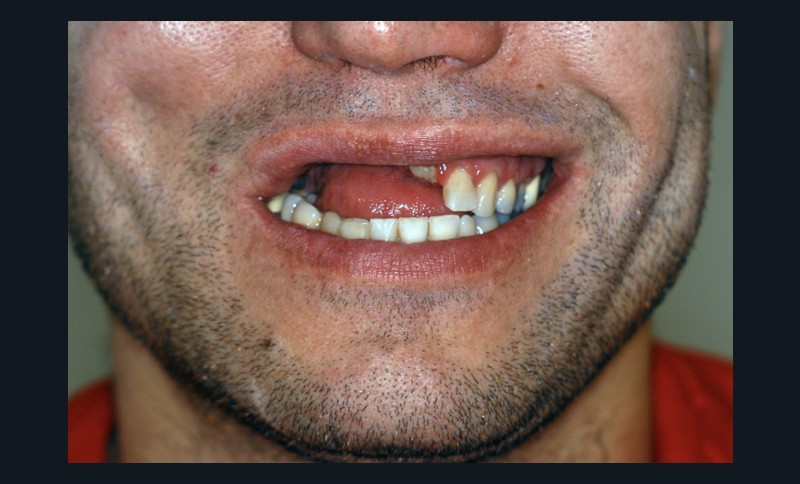

Car ce sont bien des situations cliniques exceptionnelles que ce conférencier a prises en charge, non pas seul, mais en constituant une équipe multidisciplinaire plus à même de relever les défis fonctionnels, structurels, biologiques et esthétiques en présence. Après avoir passé en revue les composants essentiels à l’obtention d’un sourire équilibré, Nadim Aboujaoude a évoqué les travers des traitements dits esthétiques mais conduits sans planification globale et qui engendrent des résultats disgracieux. Depuis de nombreuses années, l’engouement pour les solutions esthétiques ne faiblit pas. La divulgation médiatique des progrès technologiques et chirurgicaux réels encourage une part croissante de la population à recourir à des procédures souvent fiables, mais parfois portées au-delà des limites raisonnables. Ainsi, des traitements de médecine esthétique inadaptés engendrent un effet de « ligne de sourire basse » accompagné d’une exposition exagérée des incisives mandibulaires.

La demande de correction de cette anomalie esthétique incite les patientes à rechercher une compensation prothétique (à travers un abaissement des bords incisifs maxillaires visant à rendre sa visibilité au groupe incisivo-canin maxillaire) qui concoure à recomposer les rapports des étages de la face (en minorant l’étage inférieur et majorant l’étage moyen). La reprise de ces cas cliniques se révèle particulièrement délicate et repose sur une analyse rigoureuse des clefs esthétiques de l’harmonie du sourire et de son rayonnement au sein du visage.

Concernant le versant orthodontique des traitements multidisciplinaires, Nadim Aboujaoude intègre cette thérapeutique moins invasive à ses traitements multidisciplinaires sans rechercher une occlusion de classe 1 mais en privilégiant l’obtention de situations facilitant les solutions prothétiques, parodontales ou implantaires : en redistribuant et optimisant les espaces prothétiques, en corrigeant les malpositions dentaires, en remplaçant les dents compromises par les dents adjacentes, en harmonisant les contours gingivaux, en optimisant l’inclinaison des racines dentaires et en créant des volumes osseux favorables à la mise en place d’implants. À l’issue d’une présentation riche en prise en charge thérapeutique de cas complexes, le conférencier a clairement démontré que toute solution thérapeutique ne peut se concevoir et s’établir que dans une logique multidisciplinaire axée sur la concertation.